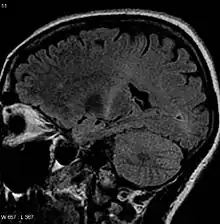

An MRI of the brain looking at a person from side-on that shows increased T2 signal as a white region in the posterior part of the internal capsule that can be tracked to the motor cortex, consistent with the diagnosis of ALS

No single test can provide a definite diagnosis of ALS.[3] Instead, the diagnosis of ALS is primarily made based on a physician's clinical assessment after ruling out other diseases.[3] Physicians often obtain the person's full medical history and conduct neurologic examinations at regular intervals to assess whether signs and symptoms such as muscle weakness, muscle atrophy, hyperreflexia, Babinski's sign, and spasticity are worsening.[3] Many biomarkers are being studied for the condition, but as of 2023 are not in general medical use.[89]